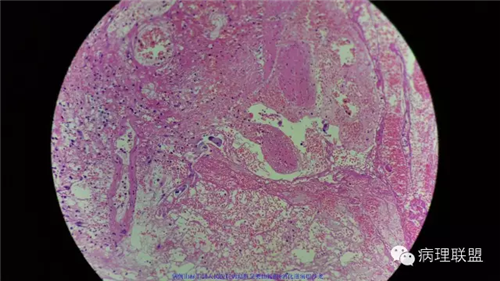

病例2

病史

女性,60岁,结肠腺瘤活检。有一灶腺体突破粘膜肌,腺体无明显异形。

(注:病例由岳阳病理吴龙云提供 致谢!)